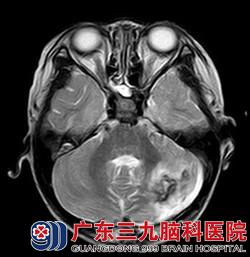

经华刚医生详细询问病史及查体后,明确患儿目前左侧小脑半球存在占位性病变。根据患者年龄结合头颅磁共振,考虑髓母细胞瘤可能性大,且病变已形成小脑扁桃体下疝,体征上已有不能走一字步,指鼻不准确、双手快速轮替运动差等症状。若肿瘤进一步生长,患者上述功能将进一步变差,甚至肿瘤严重压迫脑干,造成心跳呼吸骤停等风险。另外,因脑脊液循环通路因受肿瘤压迫,脑室内的脑脊液不能按正常途径回流,造成脑室内脑脊液过多、渗出,常常出现胡言乱语、大小便失禁、呕吐、精神反应变差等症状。患者需尽快行手术治疗,否则后果不堪设想。

看着生病的女儿情况一天比一天糟,小茹的父母心如刀割,但几万元的手术费用对一个务农的家庭来说是笔大数目。是放弃还是手术,小茹的父母内心苦苦挣扎着。在亲戚朋友劝说及帮助下,小茹父母终于筹到手术费用,为小茹办理了入院手续。接下来,医生们为小茹进行了“左侧小脑占位病变切除术+右额脑室外钻孔引流术”,术程顺利。术后病理示:髓母细胞瘤 WHO IV级。

广东三九脑科医院神经外八科华刚医生介绍,髓母细胞瘤好发于儿童,占儿童颅内肿瘤的近1/3,尤其10岁以前的小儿为发病高峰年龄。髓母细胞瘤早期症状较隐匿,一般出现头痛呕吐、步态不稳等中枢神经系统症状后才被发现。手术切除和术后放化疗是治疗该肿瘤必不可少的手段,手术应在保护脑干功能的情况下尽可能全切除肿瘤,并解决脑脊液循环通路受阻问题,解除肿瘤对脑干的压迫,避免术后脑积水,为术后短期内尽快实施放疗和化疗做好必要的准备。